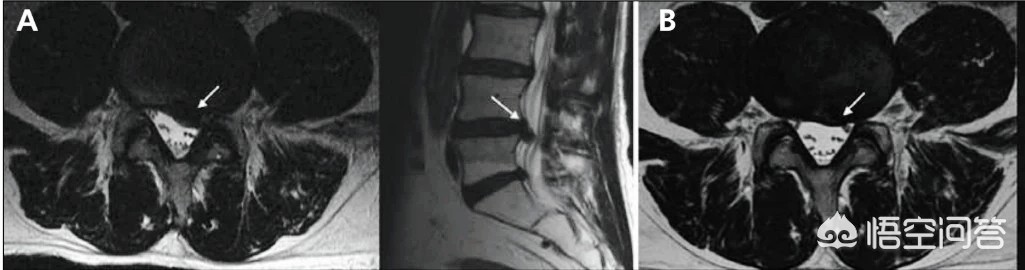

第三,椎管狭窄的患者不适合做燕飞。椎管狭窄的病人,大家从字面上就可以了解到患者椎管已经发生了狭窄。那么此时在做燕飞这样的动作的时候,脊柱是过度向后伸展的,而且我们的头向上抬,脚向上抬,腰椎的压力是比较大的,这样会使本身就已经狭窄的椎管变得更加狭窄,所以说会诱发腰椎管狭窄病人的症状加重。

第四,腰椎间盘脱出的患者不建议做燕飞。腰椎间盘脱出是比较严重的一种腰间盘突出的情况。其实就是腰椎间盘突破了保护它的纤维环掉入到了椎管内。此时不建议做燕飞和腰椎管狭窄患者,不建议做燕飞的道理是一样的。